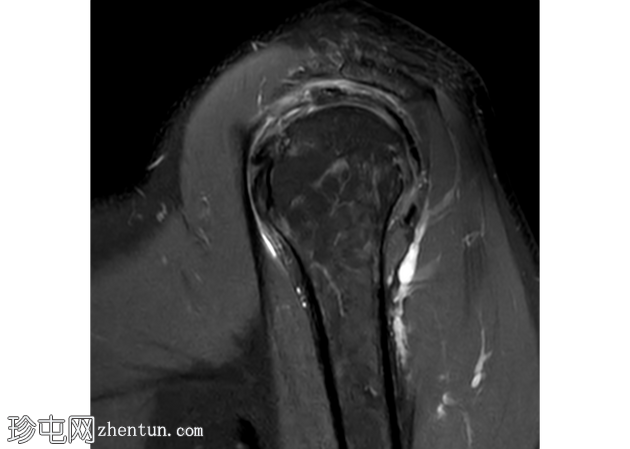

矢状面

T2

冈上肌腱滑囊侧存在部分厚度撕裂,肌腱物质内分层延伸约2厘米,与滑囊侧分层部分厚度撕裂相符。伴有间质性肩胛下肌腱(SST)撕裂。冈上肌体积轻度减少。

冈下肌腱、小圆肌腱和肩胛下肌腱完好,无明显撕裂迹象。

冠状面可见盂唇上方T2高信号,提示SLAP损伤。SLAP损伤延伸至肱二头肌长头,矢状面清晰可见。肱二头肌长头腱正常位于肱二头肌沟内,周围积液极少。

肩胛下肌隐窝和喙突下滑囊内有少量积液。

轻度肩锁关节病,特征为轻度肥大、少量关节内积液和微量肩峰下积液。

轻度盂肱关节积液。伴有肩关节囊增厚和水肿,提示反应性关节囊炎。

未发现骨髓水肿或骨折。